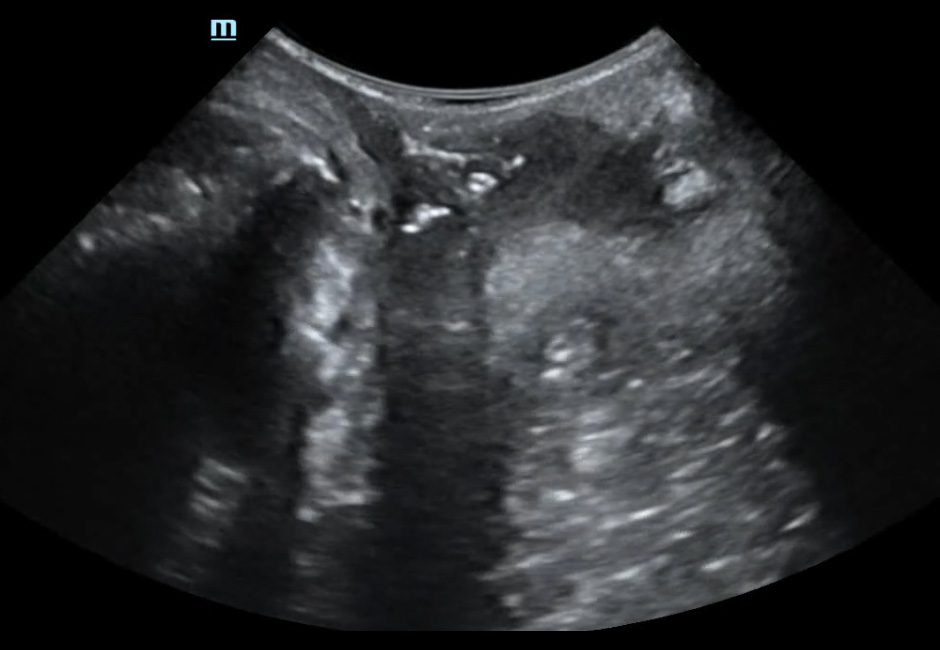

Cystocele-Bladder neck funneling-Rectocele